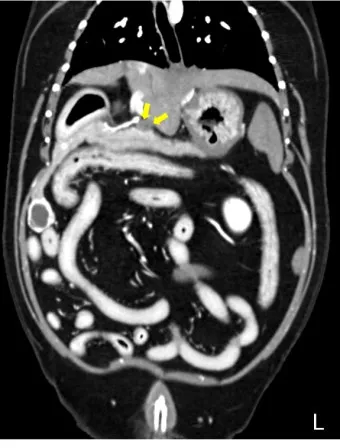

복부 초음파 검사 - 가장 기본적이면서도 중요한 1차 검사예요. 췌장의 크기나 모양 변화, 주변 장기와의 관계를 실시간으로 관찰할 수 있어요. 비용은 보통 15만원-25만원 정도이고, 검사 시간은 20-30분 정도 걸립니다.

CT와 MRI 검사 - 초음파에서 의심스러운 소견이 발견되면 더 정밀한 검사를 진행해요. 특히 3D 영상으로 종양의 정확한 위치와 크기를 파악할 수 있어서 수술 계획을 세우는 데 필수적이에요.